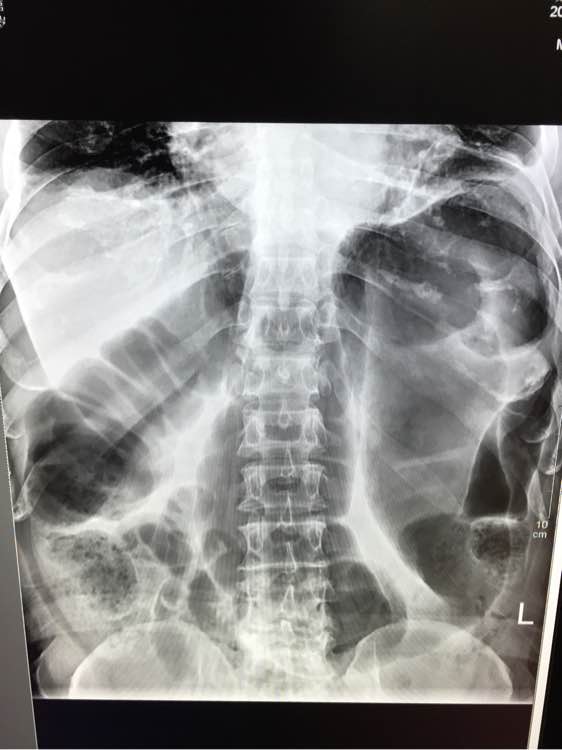

腹痛1天 从x片可以看出什么问题啊